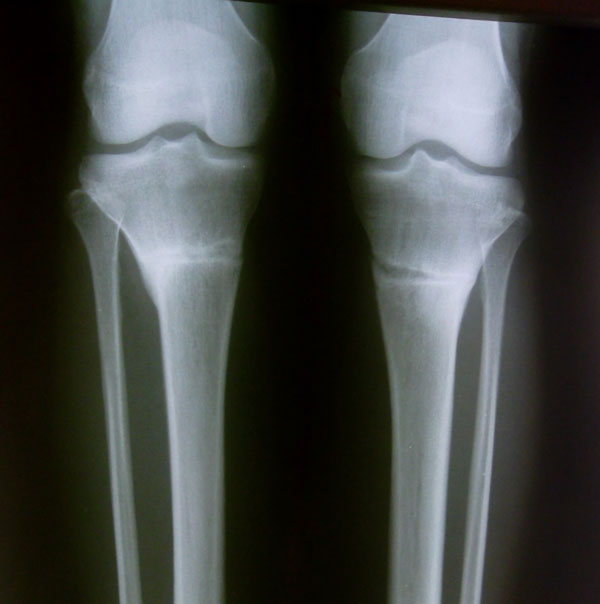

Результат

Рентгеновские снимки.

Вложения

SAM_0774.jpg

SAM_0765.jpg